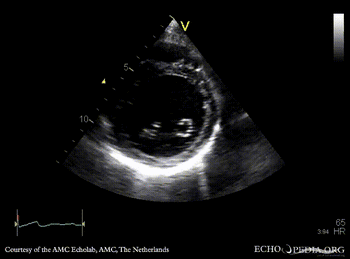

Dilated cardiomyopathy

PLAX: dilated poor left ventricle in patient who receives chemotherapy PSAX: dilated poor left ventricle